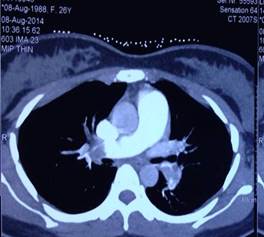

Nhân một trường hợp phụ nữ có thai 12 tuần bị tắc động mạch phổi có sốc được điều trị thành công bằng thuốc tiêu sợi huyết alteplase

TÓM TẮT  Tắc động mạch phổi cấp có tỷ lệ tử vong cao nếu không được chẩn đoán và điều trị kịp thời. Phụ nữ có thai là một trong những yếu tố nguy cơ gây TĐMP cấp. Lựa chọn phương pháp để chẩn đoán và điều trị một cách...